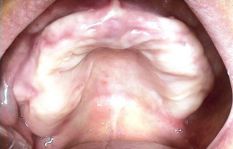

Il manque toutes les dents

Quand il y a assez d’os pour mettre suffisamment d’implants(4 à la mâchoire du bas et 4 à 6 à la mâchoire du haut), il est possible de placer immédiatement un bridge en résine sans palais.

voir le chapitre : Réhabilitation complète en 3 jours